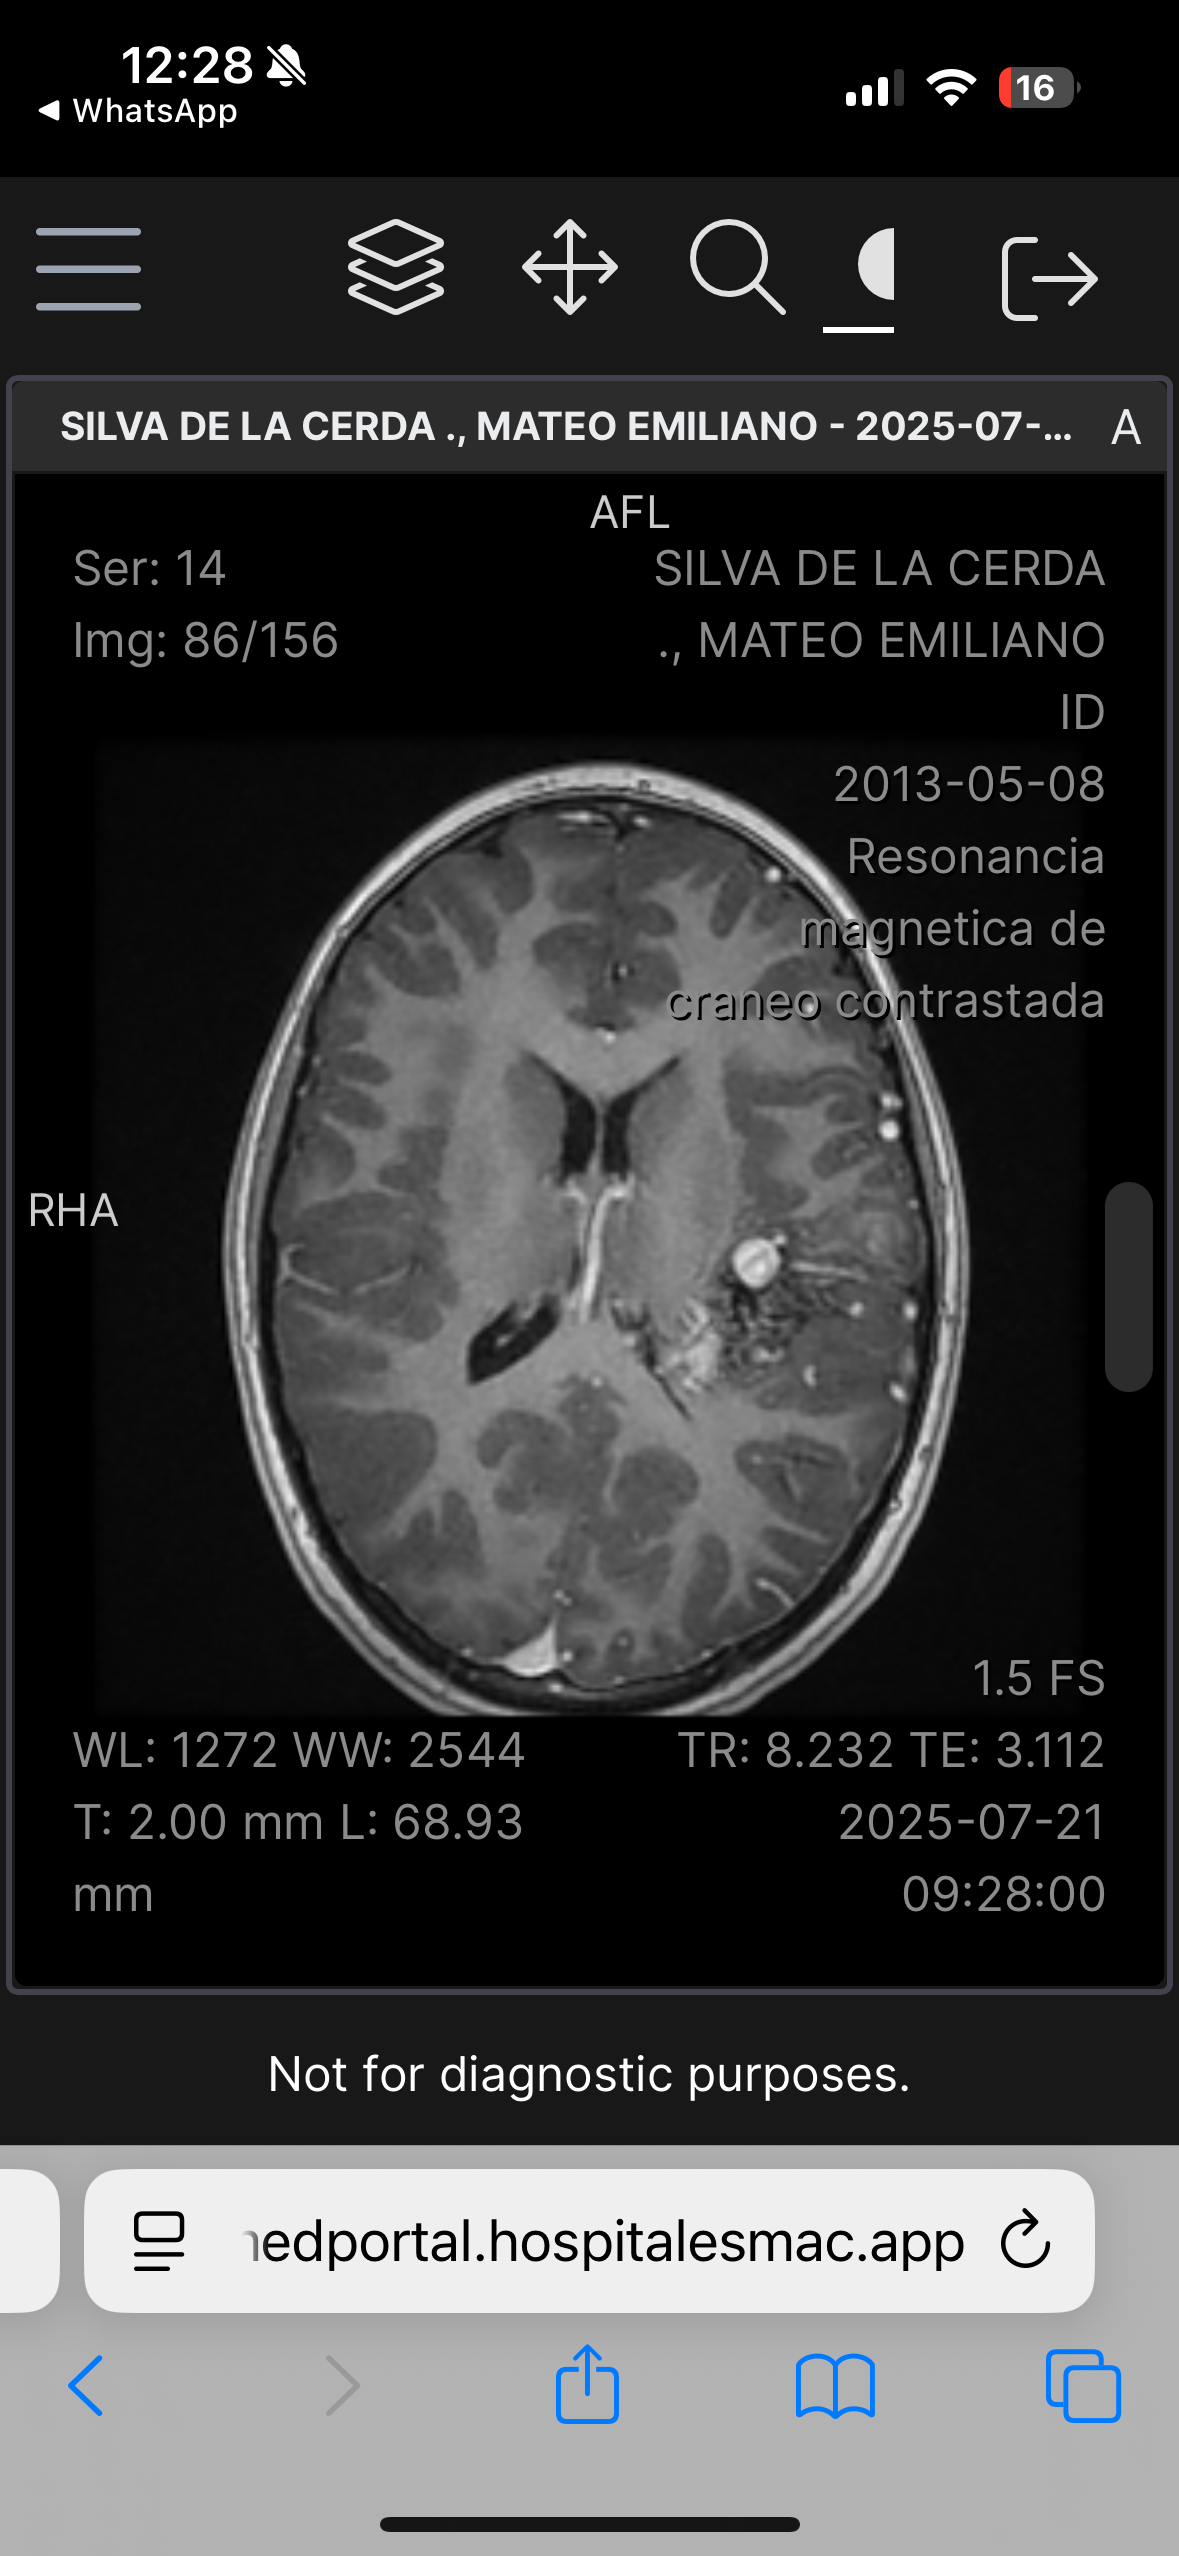

Hola, me llamo Mateo Silva De La Cerda, tengo 12 años, recientemente tuve un diagnóstico que cambió mi vida y la de mis papás, padezco una Malformación Arteriovenosa grado IV en la parte izquierda de mi cerebro, la cual hace un Nidus vascular. La complejidad de la malformación es por el aumento en la irrigación sanguínea los cual crea un tipo de “ nido” de venas y arterias, así como la profundidad en la cual se encuentra situada la malformación arteriovenosa en mi cerebro. Requiero una cirugía muy compleja, y la probabilidad de ocupar terapia intensiva posterior es muy alta.